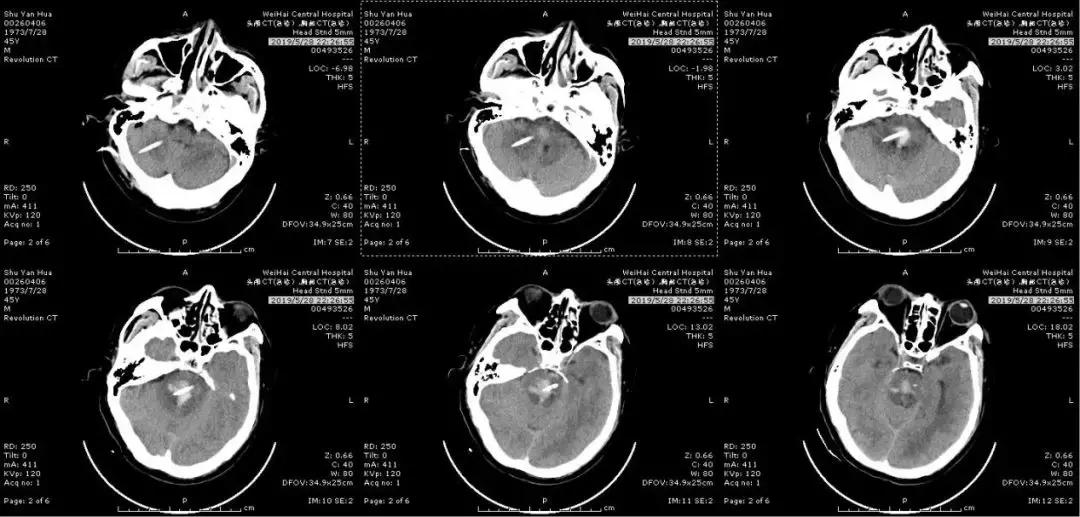

经过术前精确定位,在后枕部准确将引流管置入脑干血肿靶心,抽出血肿少许,证实引流管在血肿腔;同时,侧脑室放置一根引流管,整个手术历时1小时,手术顺利完成!立即复查头颅CT,原来脑干斑片状的高密度影较前明显减少,患者送往重症医学科观察并进一步治疗。

(术中抽出脑干部分血肿)

(术后即可复查头颅CT)